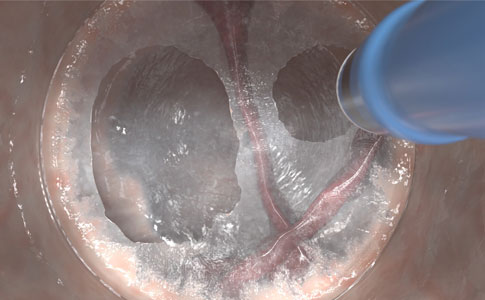

INFLEXIÓN CON ESTABILIDAD

Espere un paso suave y una longitud de electrodo estable, incluso en posiciones endoscópicas anguladas o retroflexionadas difíciles.